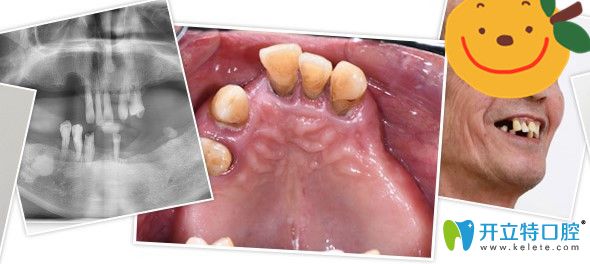

▼郭老全口種植牙前后對(duì)比照

侯國(guó)鎮(zhèn)為郭老做全口種植牙前后對(duì)比照

▼沒(méi)有做種植牙前

沒(méi)有來(lái)廣州廣大口腔做種植牙前

其實(shí)郭老之前剛?cè)毖赖臅r(shí)候做過(guò)活動(dòng)假牙,但是因?yàn)楫愇锔袕?qiáng)烈,并不怎么佩戴,因?yàn)槊撀溲例X周邊沒(méi)有支撐,慢慢的,他的牙齒都逐漸脫落松動(dòng),到他決定做種植牙前,他全口只剩上面5顆牙,下面4顆牙和一顆殘根,而且全都松動(dòng)的很厲害,吃東西嚼不爛,非常痛苦。

牙齒情況:全口僅剩9顆牙和一顆殘根